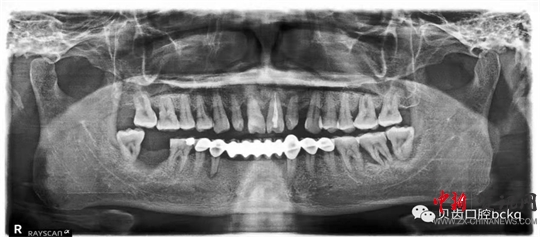

下面這兩張x光片是比較典型的牙周炎的影像資料。該患者的全口所有牙齒都出現了不同程度的松動;颊攥F在感覺無法用牙齒咀嚼。坦白地講,牙周炎發(fā)展到這種程度,很多時候醫(yī)生也束手無策了。為了保留更多的牙槽骨,醫(yī)生回不得不拔掉哪些嚴重松動的患牙。